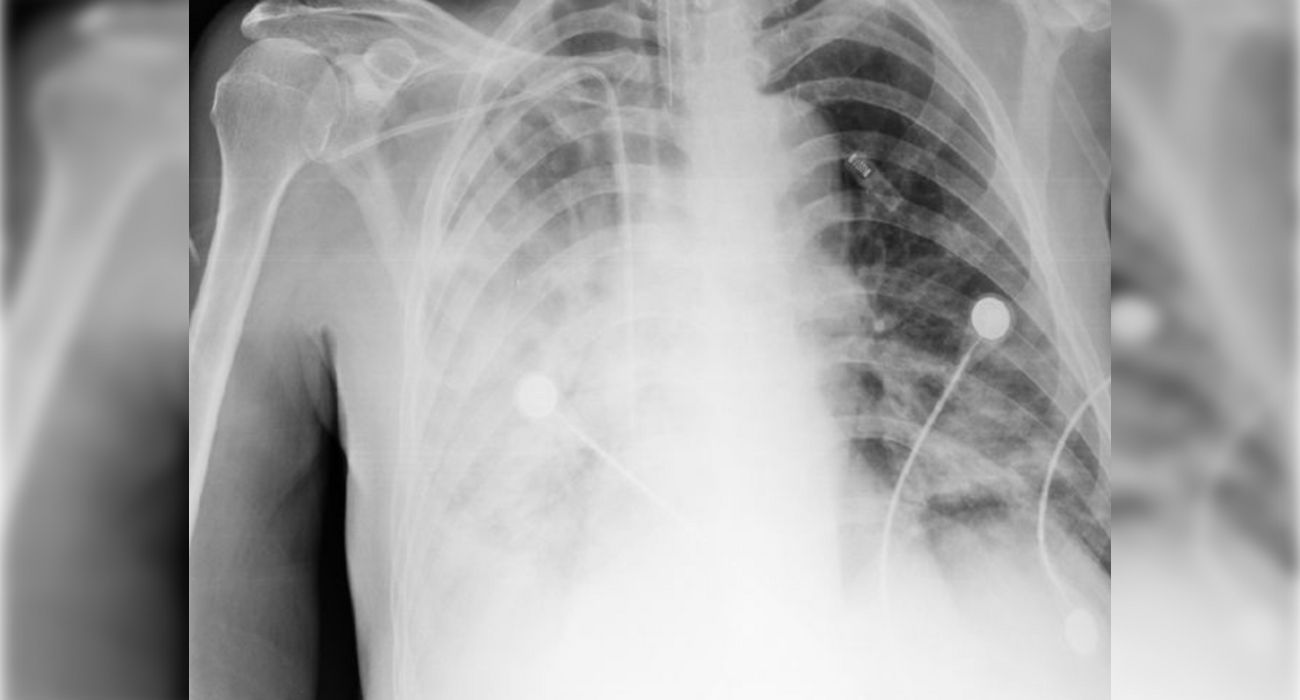

La melioidosis suele afectar a los pulmones en la versión aguda de la enfermedad, aunque también otros órganos pueden sufrir complicaciones.

Las manifestaciones clínicas pueden ir desde neumonía o bronquitis a abscesos benignos o una septicemia con consecuencias fatales.